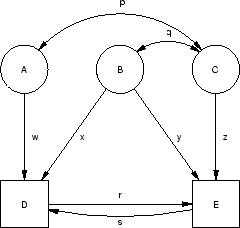

5 Path Models for Linear Regression

Figure 5.2:

Regression path models with manifest variables.

In this Section we attempt to clarify the conventions, the assumptions

and the tracing rules of path analysis by applying them to regression

models. The path diagram in Figure 5.2a

represents a linear regression model, such as might be used, for

example, to predict systolic blood pressure [SBP],  from sodium

intake

from sodium

intake  . The model asserts that high sodium intake is a

cause, or direct effect,

of high blood pressure (i.e., sodium intake

. The model asserts that high sodium intake is a

cause, or direct effect,

of high blood pressure (i.e., sodium intake  blood

pressure), but that blood pressure also is influenced by other,

unmeasured (`residual'), factors. The regression equation represented

in Figure 5.2a is

We can extend the model by adding more independent variables or more

dependent variables or both. The path diagram in Figure 5.2b

represents a multiple regression model, such as might be used if we

were trying to predict SBP (

Figure 5.2c represents a multivariate regression model, where

Figure 5.2c represents a multivariate regression model, where

Figure 5.2d differs from Figure 5.2c only by the

independent variables. Figure 5.2e adds an additional causal